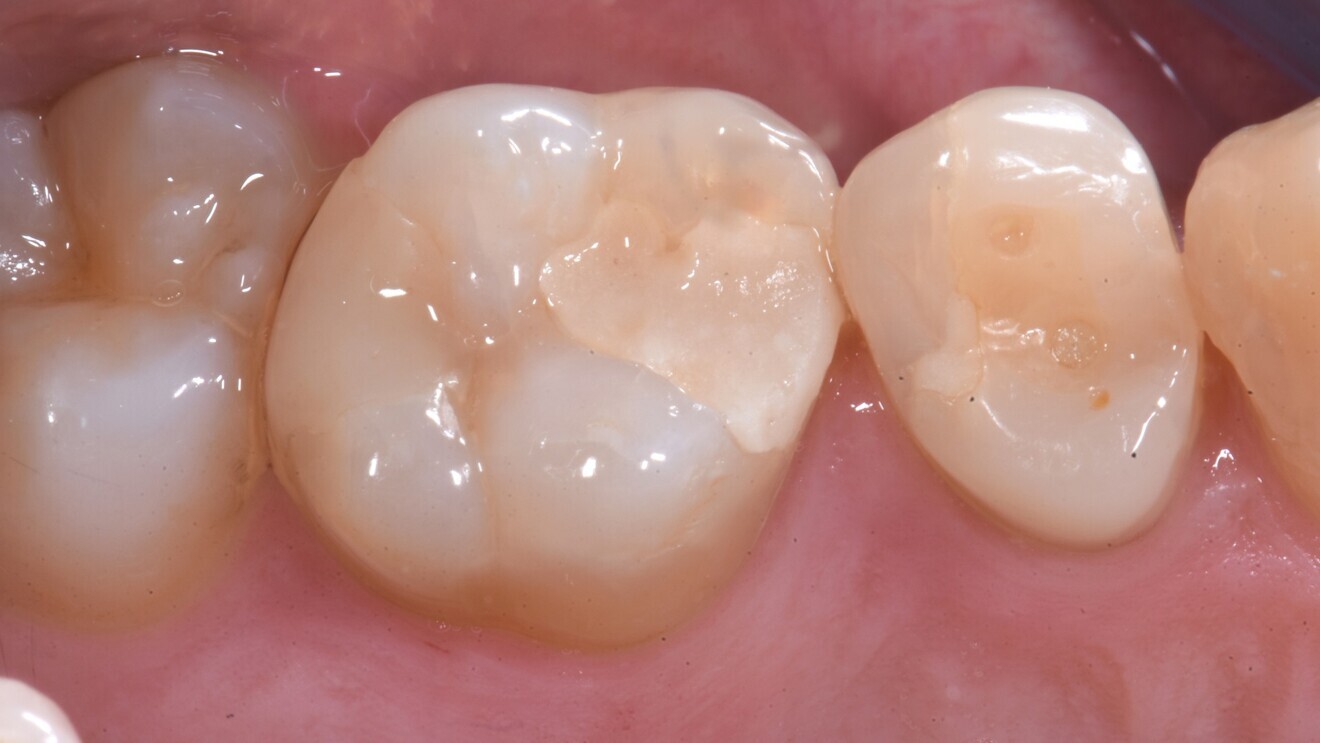

Fig. 5: Class I glass hybrid restoration with EQUIA Forte after placement.

Fig. 6: Glass hybrid restoration at follow-up, three years after placement.

In the first trial, a glass hybrid (EQUIA Forte), a bulk fill composite resin (Filtek Bulk Fill Posterior Restorative, 3M) and a micro-hybrid composite resin placed incrementally (Charisma Smart, Kulzer) were compared.8 In total, 109 teeth in 54 rather young patients (31 female, 23 male; mean age: 22 years) with two-surfaced (mesio-occlusal, disto-occlusal) cavities in permanent teeth were randomly restored. The restorations did not extend towards cusps and all cervical margins were placed in sound enamel (i.e. not subgingivally). After caries removal and minimally invasive preparation, the materials were placed. After up to 24 months, 84 restorations were evaluated using the modified USPHS criteria. Composite restorations showed better anatomical form, contact points, colour matching, surface texture and overall survival compared with the glass hybrid restorations.